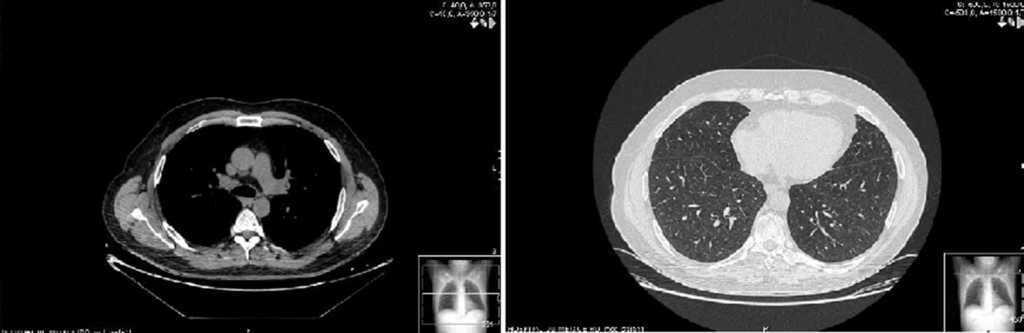

Two weeks later, the patient presented clinical improvement (after drug treatment with antibiotics and bronchodilators) but with persistent injury in chest radiography, so a thoracic CT was performed, showing bilateral and diffuse ground-glass opacities, multiple centrilobular micronodules (Figure 1) and mediastinal lymphadenopathy. Bronchoscopy was normal, and transbronchial biopsy showed the presence of non-necrotizing granulomas. Ziehl Neelsen, and Groccott staining were negative, as PCR and mycobacteria culture. After completing HCV treatment, the clinical course of the patient was favorable, showing the following thoracic CT gradual improvement in lung and lymph node involvement, and finally, a year later, the resolution of the disease (Figure 2).

Figure 1. Sarcoidosis in 50 years-old man, coinfected with HIV and HCV, and treated with telaprevir-based triple therapy. Thin-section of thoracic CT shows bilateral and diffuse ground-glass opacities, and multiple centrilobular micronodules.